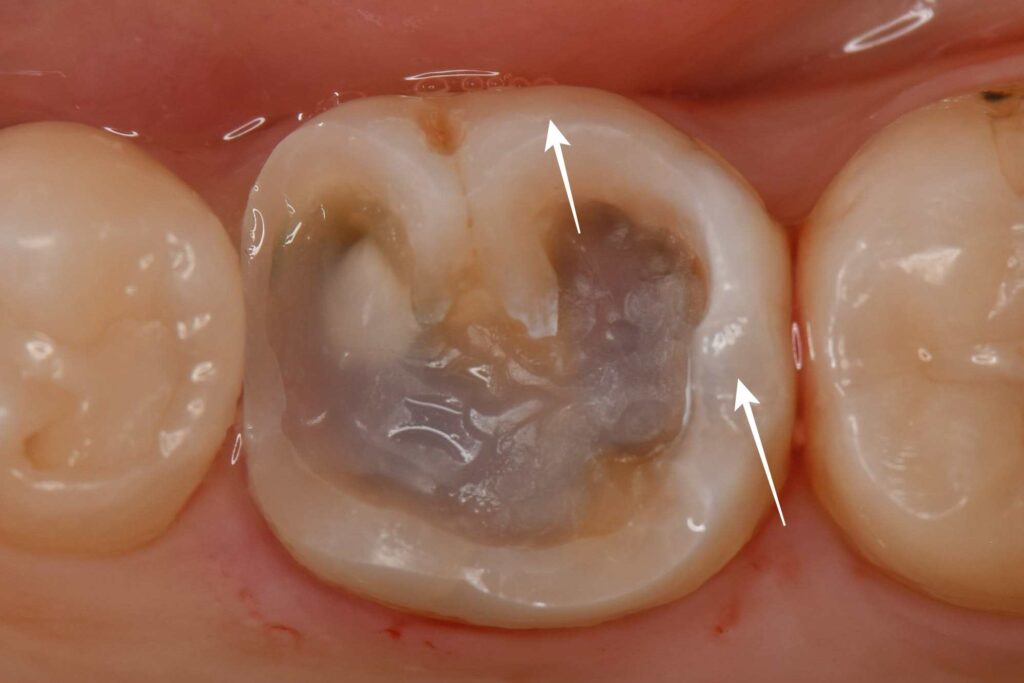

この大きさの虫歯は、通常全体を削って被せることでセラミックが割れるリスクを減らすのですが、ご本人様のご希望もありできるだけ歯を削らずに白矢印部を残す形でセラミック(オーバーレイ)を作成しました。

セラミックインレーは素材によってジルコニアとemaxの2種類があり、今回はより適合性が良い(隙間が少ない)emaxインレーを選択しました。

e-maxインレーはジルコニアインレーに比べ強度は劣りますが、歯とセラミックとの隙間が最小限で抑えられるため虫歯予防効果が期待できます。

また、e-maxの作成方法は削り出しではなく、鋳型に合わせてセラミックを射出・プレスするタイプの「e-max press」で作成し、更に隙間を減らす工夫をしております。